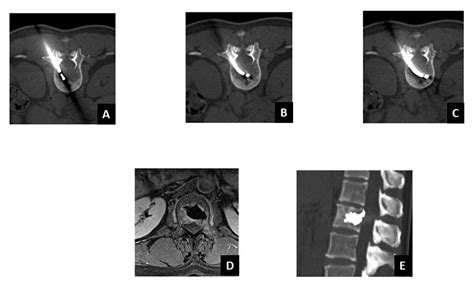

Cooled radiofrequency ablation relieves arthritis pain in shoulder and hip

The Role of a Navigational Radiofrequency Ablation Device and ...

mdpi.com